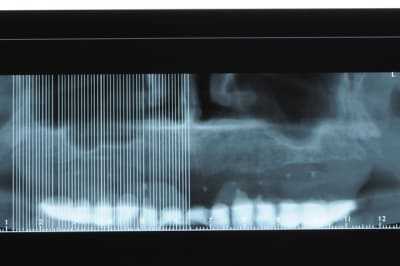

j'ai besoin de 4 implants au maxillaire pour faire tenir son complet.

dans la zone postérieur, pas de problème, mais devant, c'est une autre histoire.

avant de faire la tomosynthèse je comprenais pas pourquoi j'avais aussi peu de contraste.

le patient ne souhaite pas, ou ne peut pas se faire poser 6 implants en haut, donc...overdenture sur 4. (si possible)